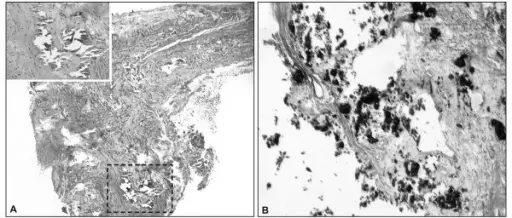

Tertiary syphilis is a common cause of thoracic aneurysm.

Tertiary syphilis can cause vasa vasorum endarteritis leading to thoracic aneurysm due to:

- Luminal constriction

- Reduced blood flow

- Vascular wall atrophy

Tertiary syphilis results in the aorta having a “tree-bark” look.